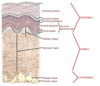

What are the layers of the Epidermis?

What are the layers of the dermis?

What are the layers of the hypodermis?

Where should melanocytes be located?

Basal Layer